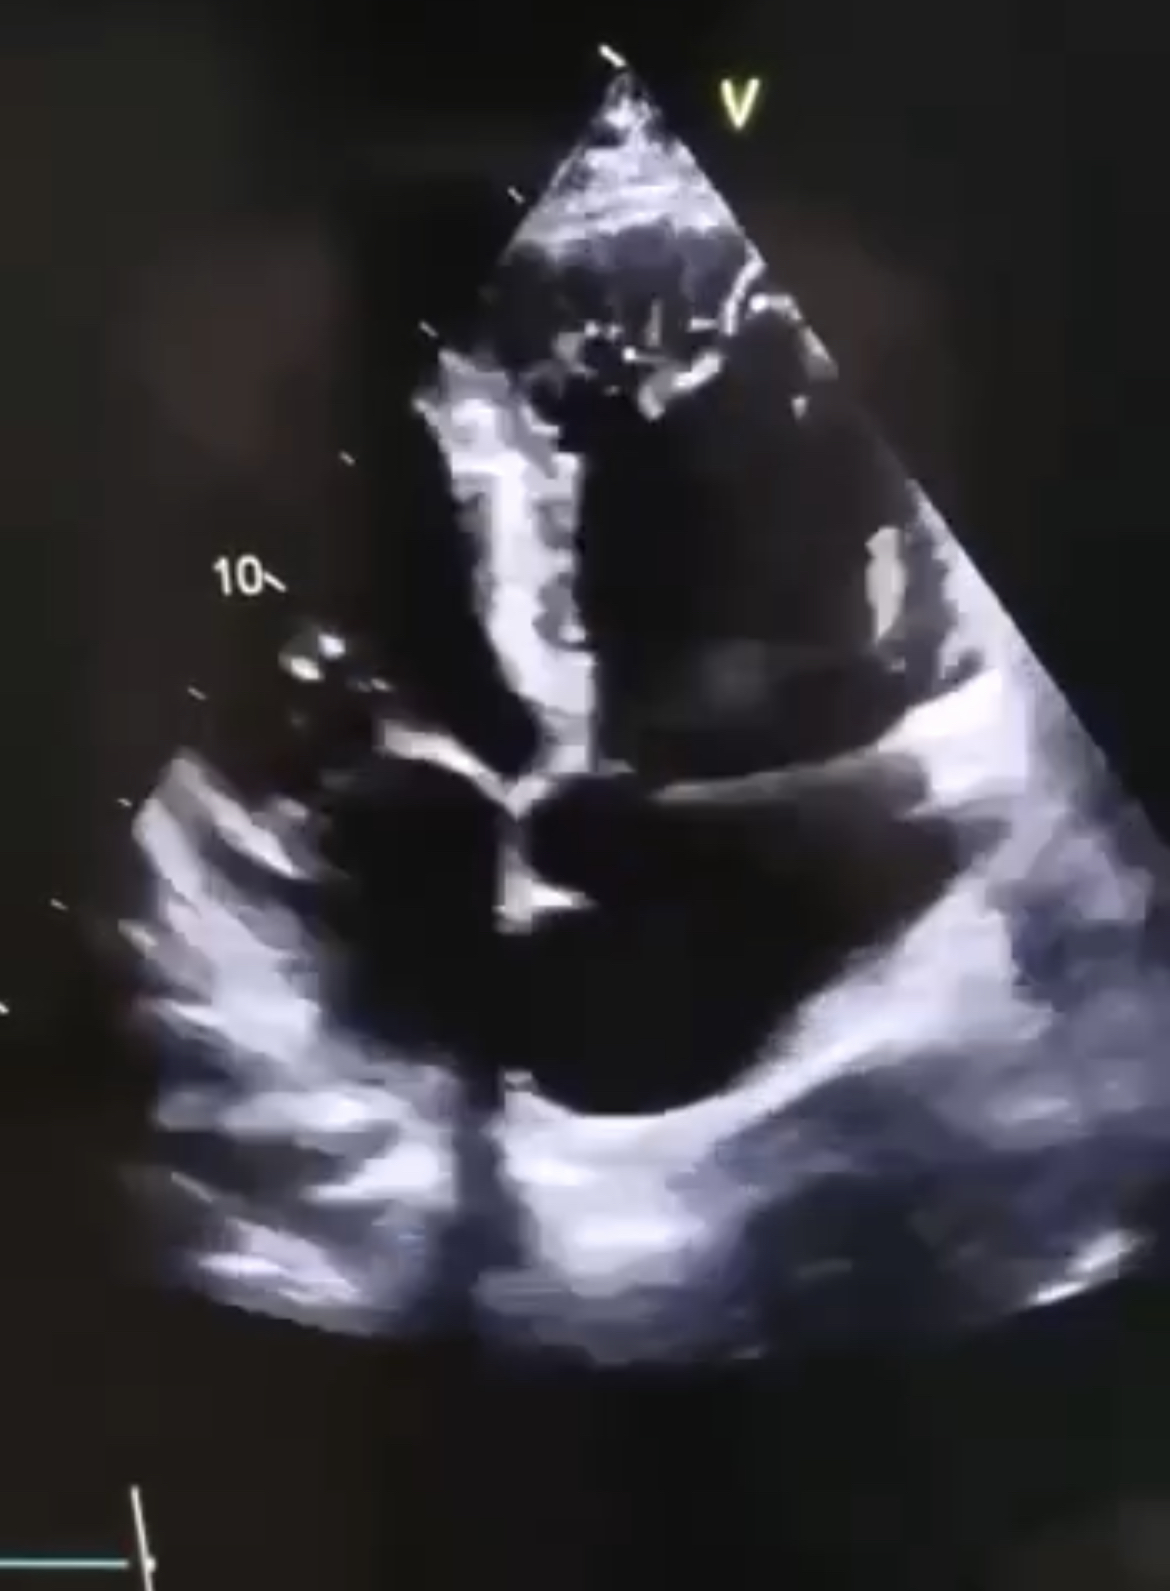

Так что кому плющевые сердца , а кому и настоящие , к